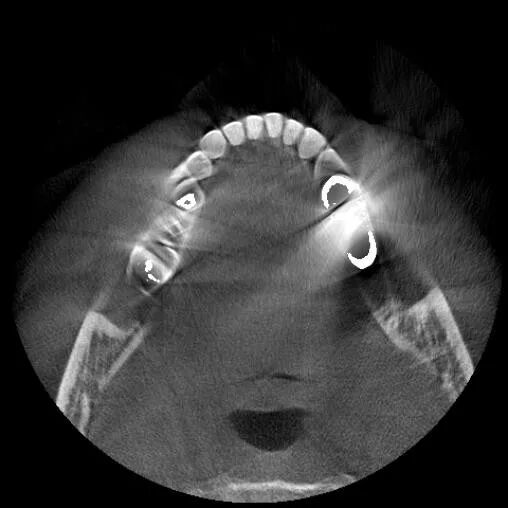

OnDemand 3D后處理軟件直接模擬真實(shí)種植場(chǎng)景,更有骨密度精確測(cè)量,醫(yī)患溝通更直觀,手術(shù)更安全,患者更信任。

“伯爵Bondream”智能3D全景由外向內(nèi)33張全景片觀查

骨密度精確測(cè)量